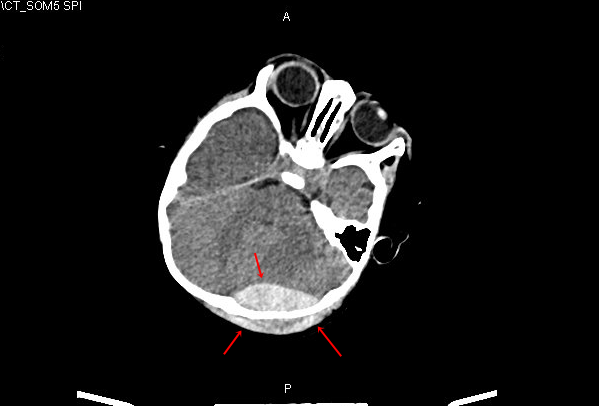

Hình ảnh chụp cắt lớp vi tính máu tụ sọ não của bệnh nhi 11 tháng tuổi

Qua kết quả thăm khám lâm sàng và hình ảnh chụp cắt lớp vi tính, các bác sĩ chẩn đoán bé C. bị chấn thương sọ não, máu tụ ngoài màng cứng đỉnh chẩm trái. Sau khi hội chẩn đa chuyên khoa Nhi, Gây mê hồi sức, Phẫu thuật Thần kinh – Cột sống, các bác sĩ chỉ định phẫu thuật cấp cứu mở hộp sọ lấy máu tụ, cầm máu và ghép lại ngay xương sọ cho bệnh nhi.